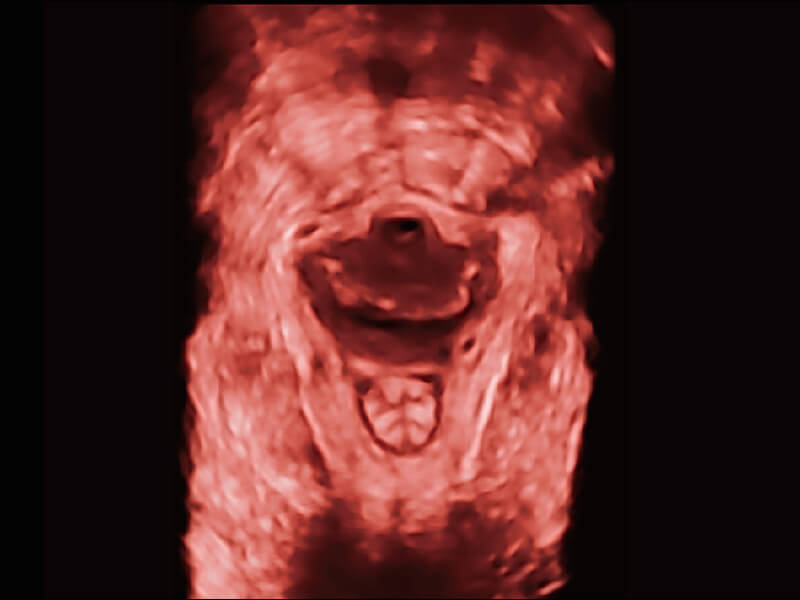

高分辨率容积成像 栩栩如生

超宽频带技术,为容积成像带来优质的二维图像基础,为您呈现丰富的结构细节,栩栩如生地展示宝宝的宫内形态以及各种组织的立体结构。